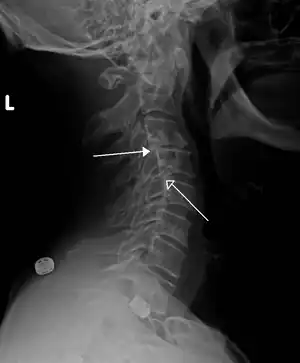

A hangman's fracture is a specific type of spondylolisthesis where the second cervical vertebra (C2) is displaced anteriorly relative to the C3 vertebra due to fractures of the C2 vertebra's pedicles.

A retrolisthesis is a posterior displacement of one vertebral body with respect to the subjacent vertebra to a degree less than a luxation (dislocation). Retrolistheses are most easily diagnosed on lateral x-ray views of the spine. Views, where care has been taken to expose for a true lateral view without any rotation, offer the best diagnostic quality.

Retrolistheses are found most prominently in the cervical and lumbar region, but can also be seen in the thoracic area.